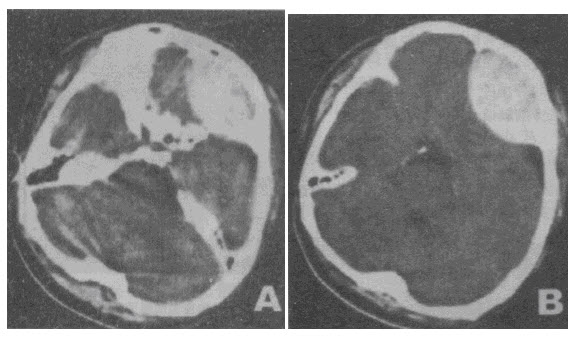

男性,55岁。被汽车撞倒半小时,昏迷状态。急诊平扫CT。检查图像如图所示,诊断最

[单选题]男性,55岁。被汽车撞倒半小时,昏迷状态。急诊平扫CT。检查图像如图所示,诊断最可能是()A . 脑实质出血B . 正常脑CT表现C . 硬膜下血肿D . 硬膜外血肿E . 蛛网膜下隙出血

男性,55岁。被汽车撞倒半小时,昏迷状态。急诊平扫CT。检查图像如图所示,诊断最可能是( )。<br /><img border="0" style="

[单选题]男性,55岁。被汽车撞倒半小时,昏迷状态。急诊平扫CT。检查图像如图所示,诊断最可能是( )。A.脑实质出血B.正常脑CT表现C.硬膜下血肿D.硬膜

男性,55岁。被汽车撞倒半小时,昏迷状态。急诊平扫CT。检查图像如图所示,诊断最可能是<img border="0" style="width: 264px; he

[单选题]男性,55岁。被汽车撞倒半小时,昏迷状态。急诊平扫CT。检查图像如图所示,诊断最可能是A.脑实质出血B.正常脑CT表现C.硬膜下血肿D.硬膜外血肿E.

男性,55岁。被汽车撞倒半小时,昏迷状态。急诊平扫CT。检查图像如图所示,诊断最可能是<img border="0" style="width: 264px; he

[单选题]男性,55岁。被汽车撞倒半小时,昏迷状态。急诊平扫CT。检查图像如图所示,诊断最可能是A.脑实质出血B.正常脑CT表现C.硬膜下血肿D.硬膜外血肿E.

男性,55岁。被汽车撞倒半小时,昏迷状态。急诊平扫CT。检查图像如图所示,诊断最可能是<img border="0" style="width: 264px; he

[单选题]男性,55岁。被汽车撞倒半小时,昏迷状态。急诊平扫CT。检查图像如图所示,诊断最可能是A.脑实质出血B.正常脑CT表现C.硬膜下血肿D.硬膜外血肿E.